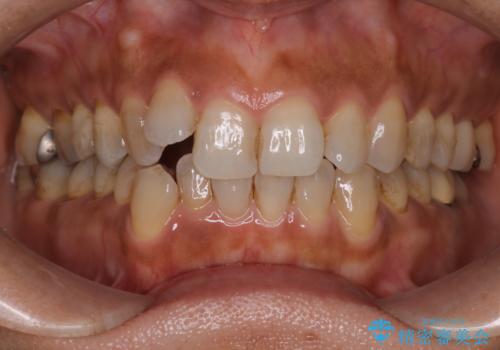

20代男性 ハーフリンガルによる抜歯矯正

- 上下の歯のでこぼこと、出っ歯感を改善したいとの主訴で来院されました。

上下両側の前から4番目の抜歯をして治療をしていくこととなりました。

骨格的に上顎より下顎が後退しているため、少々上の前歯が内側に倒れこんでいる印象になった仕上がりとなっております。